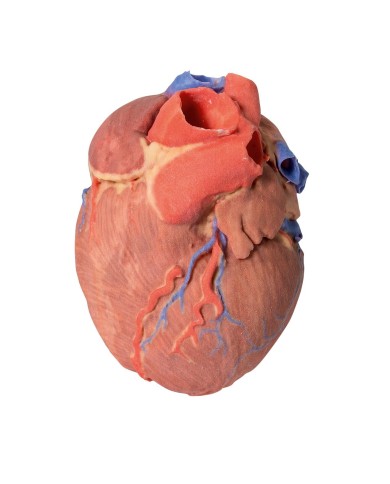

I modellini anatomici di cuore umano sono strumenti indispensabili per uno studio corretto dell'anatomia del cuore umano.

Su Tuttoanatomia trovi la più ampia selezione di prodotti esistente sul web, che va dai cuori normali ai cuori affetti da patologie, per aiutarti a comprendere come le patologie cardiache influiscono e modificano la struttura anatomica cardiaca.

Su Tuttoanatomia trovi la più vasta selezione online, certamente abbiamo il modello di cuore più adatto alle tue esigenze. I cardiologi e gli studenti acquistano i modelli anatomici di cuore umano per studiare nei minimi dettagli la struttura anatomica del cuore umano, ma anche per dare spiegazioni ai propri pazienti, per illustrare visivamente la patologia di cui sono affetti, ed il tipo di intervento che si intende eseguire durante la terapia. Le quotazioni su Tuttoanatomia sono le più convenienti del mercato e la qualità dei prodotti è davvero eccezionale, in modo da offrirti un rapporto qualità prezzo incomparabile.